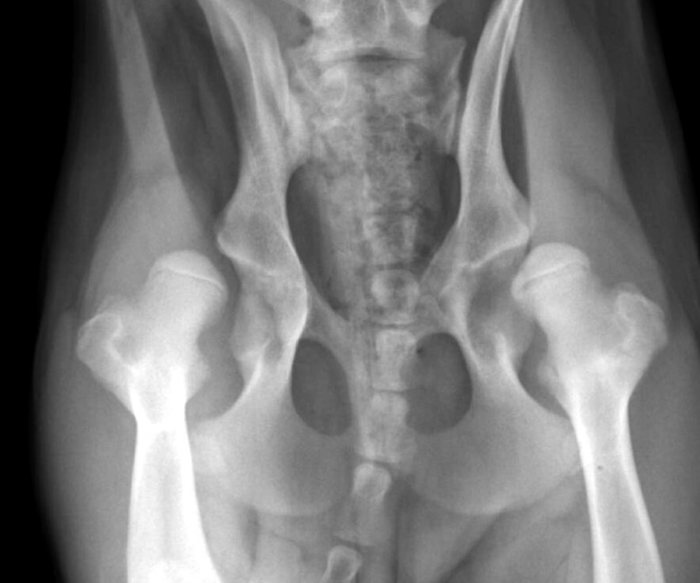

La displasia de cadera: qué es y cómo detectarla.

La displasia de cadera es una patología ortopédica hereditaria de evolución lenta que se caracteriza por un desacoplamiento en el desarrollo de la cabeza femoral y el acetábulo. En la cadera del perro, como ocurre también en la de cualquier persona, el fémur debe encajar correctamente en la cadera. De alguna manera, podría decirse que…